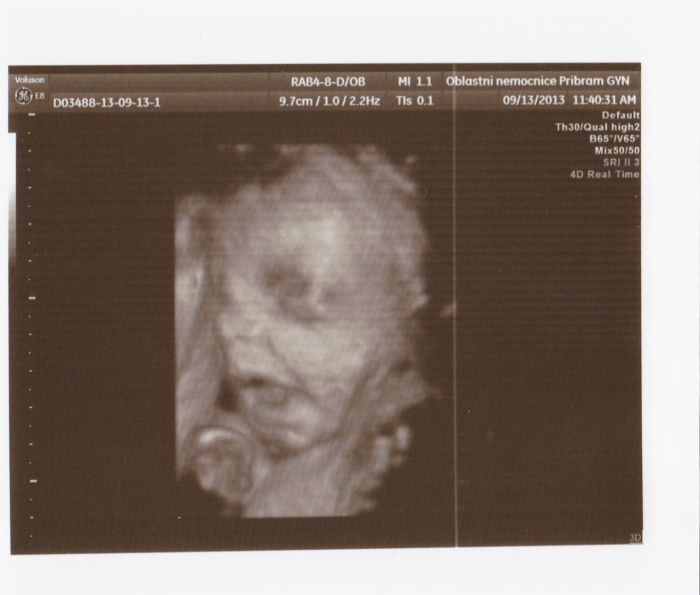

Autor: Martina 127 19.9.2013 v 15:21

taky posilam fotecky z 3D konecne jsem nasla kabel a povedlo se mi je dat do tabletu :-)